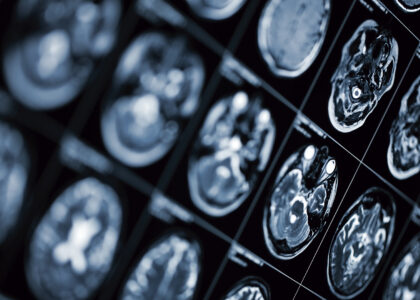

Qué es la Esclerosis múltiple El Dr. Santiago Isa nos actualizó sobre novedades en Resonancia